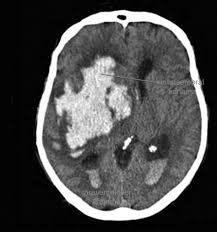

TETKİK VE TEŞHİS

Daha büyük çocuklarda ve yetişkinlerde;

Doktorunuz semptom ve bulguları değerlendirdiğinde hidrosefaliden şüphelenirse tanıyı koymadan önce ayrıntılı bir şekilde hastalığın gidişatını öğrenmeli, ayrıntılı bir fiziksel ve nörolojik inceleme yapmalı, CT veya MRG ile görüntüleme yapmalıdır. Tetkikler sonucunda hidrosefali teşhisi konursa hasta daha ileri tetkik ve tedavi için beyin cerrahi uzmanına refere edilmeli.